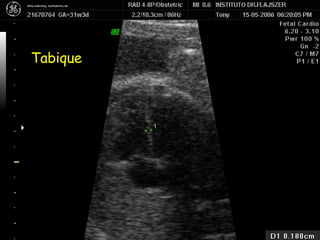

Tabique